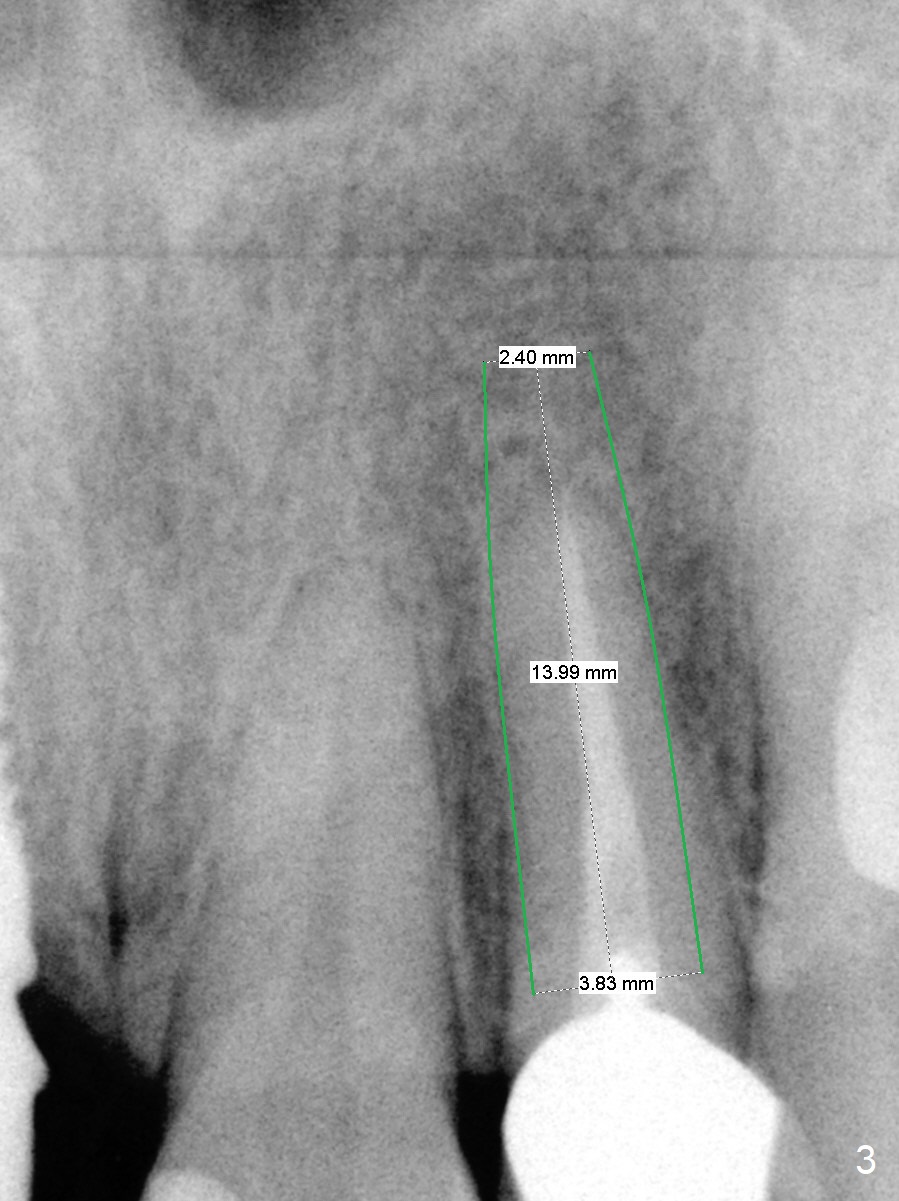

A 37-year-old woman needs an implant at #10 because of crown recementation twice (Fig.1). The smallest 2-piece implant, 3.8 mm, appears to be larger than the root. The implant may perforate the buccal apical concavity (Fig.2 arrowheads). Measure the extracted root. If it is wider than 3.8 mm mesiodistally, place the 2-piece implant. Otherwise use a 3 mm 1-piece one. Do not forget the angled one. Retrospectively, the 3.8 mm implant is large for the site. A 3.0 or 2.5 mm one is more appropriate (Fig.2).